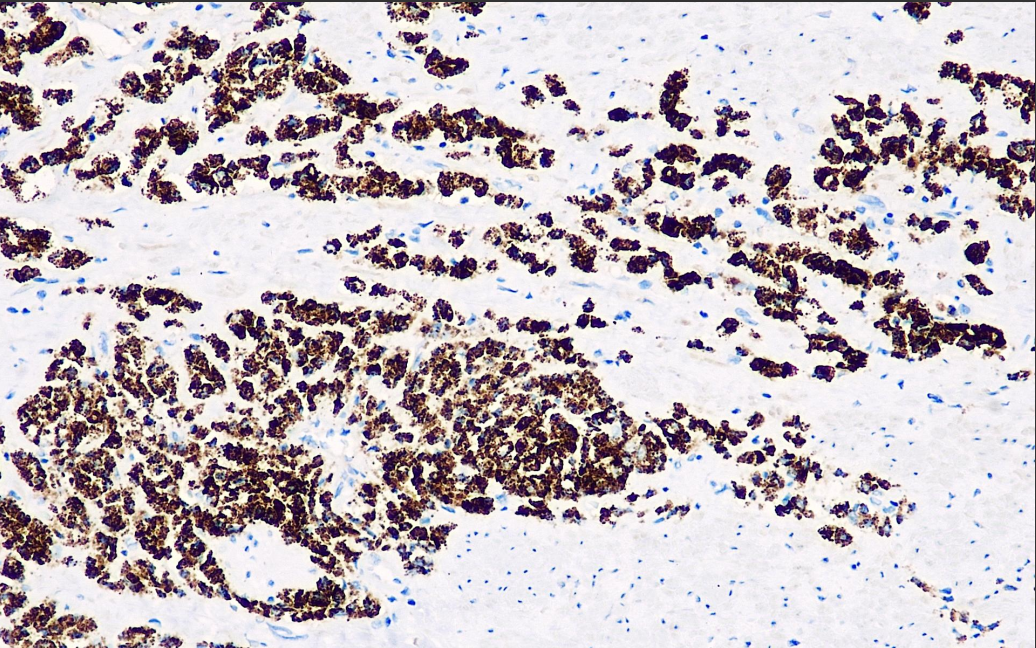

Positive control: Prostate cancer

AMACR is expressed in prostate adenocarcinoma, and also in precancerous lesions of the prostate, such as high-grade prostatic intraepithelial neoplasia and atypical adenomatous hyperplasia, and negatively in benign prostate tissue. In the diagnosis of prostate cancer, it is usually used in combination with PSA, CK (34bE12) and p63.

The p504S Antibody Reagent binds specifically to the p504S molecular antigen. Immunohistochemistry kits containing the p504S Antibody Reagent are suitable for the precise diagnosis of prostate adenocarcinoma.